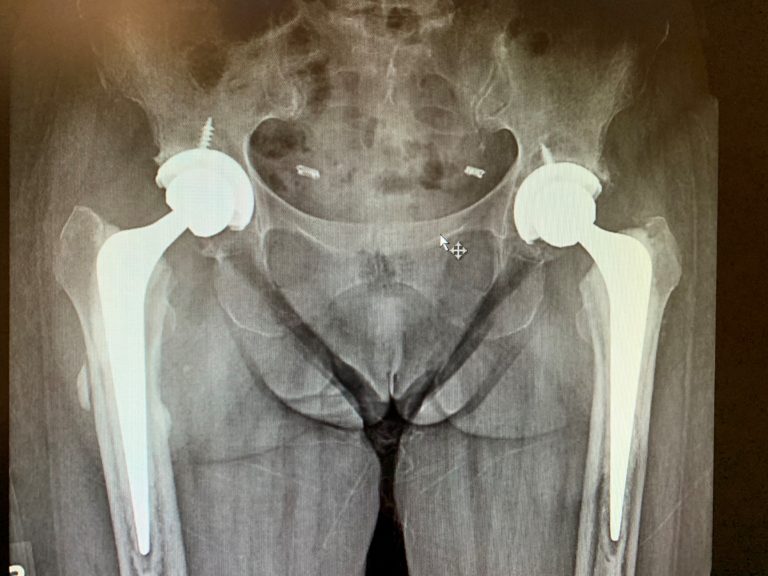

From pushpclinic.com

Bilateral hip avascular necrosis patient operated bilateral total hip How Long To Recover From Bilateral Hip Replacement If your hip replacement is done on an outpatient basis, you will go home on the same day as. “if you suffer from severe arthritis in both hips, you could get both joints replaced at the same time (double hip replacement). Full recovery from a hip replacement varies from person to person, but most people are doing well three months. How Long To Recover From Bilateral Hip Replacement.